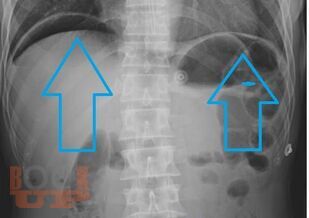

Учебно-методическое пособие посвящено проблемам лечения открытых и закрытых повреждений живота. Представлены классификации и характеристики ран, их современная диагностика, а также виды оперативных вмешательств при различных видах повреждений живота. Издание иллюстрировано рисунками, таблицами, имеются тестовые задания и задачи. Пособие предназначено для ординаторов, обучающихся по специальности 31.08.67 Хирургия и слушателей дополнительного профессионального образования.